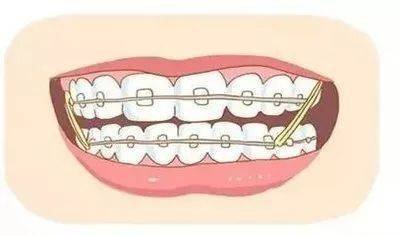

三、通过正畸改善

牙缝过大应该及时治疗。在青春期,治疗牙齿畸形需佩戴普通的正畸矫正器。对于成人而言,牙齿稀疏型正畸患者可以选择隐形正畸技术,以方便日常工作和生活。

牙齿矫正一般会在牙齿排齐后,关闭上牙齿之间的缝隙。借助橡皮筋,它会给予牙齿牵引力,继而牙齿就会把这个力传递给牙槽骨。 而牙槽骨终生是在移动的,当它接收到这种力的时候,就会产生相应的吸收或者再生过程,牙齿也会因此产生移动,缝隙就在不知不觉中逐渐变小。

对于青春发育期的青少年来说,骨改建比较活跃,甚至可以利用孩子颌骨的生长潜能辅助收缝; 这就是为什么医生更建议青少年趁早矫正的原因。 当然,牙齿矫正太快是不可取的,要靠医生把握好节奏。 所以,找一个具备精湛正畸 技术和丰富临床经验的正畸医生,是非常重要的。